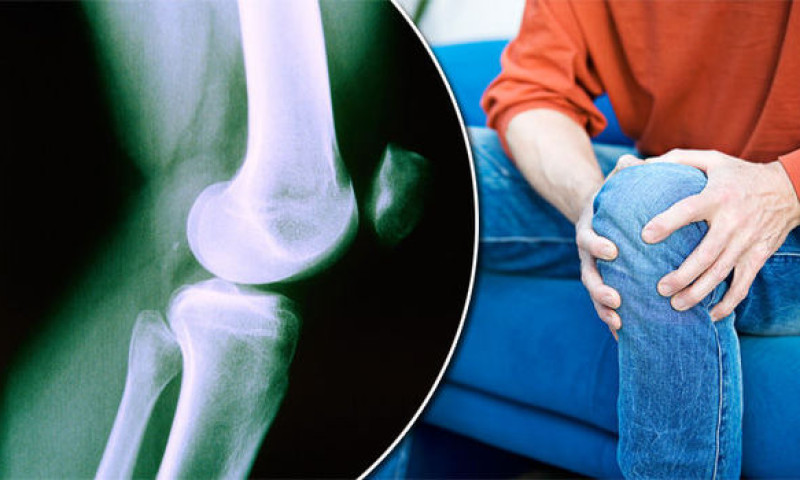

पछिल्लो समय हड्डी खिइने रोगको धेरै चर्चा हुने गरेको छ । मानिसको उमेर ढल्केसँगै हड्डीहरु खिइन्छन् भन्ने थाहा भए पनि यसलाई रोग नभएर सामान्य प्राकृतिक प्रक्रियाको रुपमा लिने गरिन्थ्यो । ‘हड्डी पनि खिइन्छ र ?’ भन्ने धारण धेरैमा थियो तर अहिले यो एक रोगको रुपमा परिचित भएको छ । हड्डी किन खिइन्छ ? र यसबाट बच्ने उपाय के के हुन् ? हाड जोर्नी विशेषज्ञ डाक्टर सगुन कुमार जोशीको सुझाब यस्तो छ :

स्वस्थ शरीरको लागि हड्डीको ठुलो भूमिका रहेको हुन्छ । मानिस अपांग हुने प्रमुख कारण मध्ये हड्डीले आवश्यक काम नगर्नु पनि एक हो । हड्डी परिपक्क वा बलियो हुने भनेको २५ देखि ३५ वर्षको उमेर सम्म हो ।

हड्डी खिइने रोग धेरैमा हुन्छ । उमेर बढ्दै जादा वा ४०/५० वर्ष पुगेसँगै यो रोगले बढी च्याप्ने गर्दछ ।